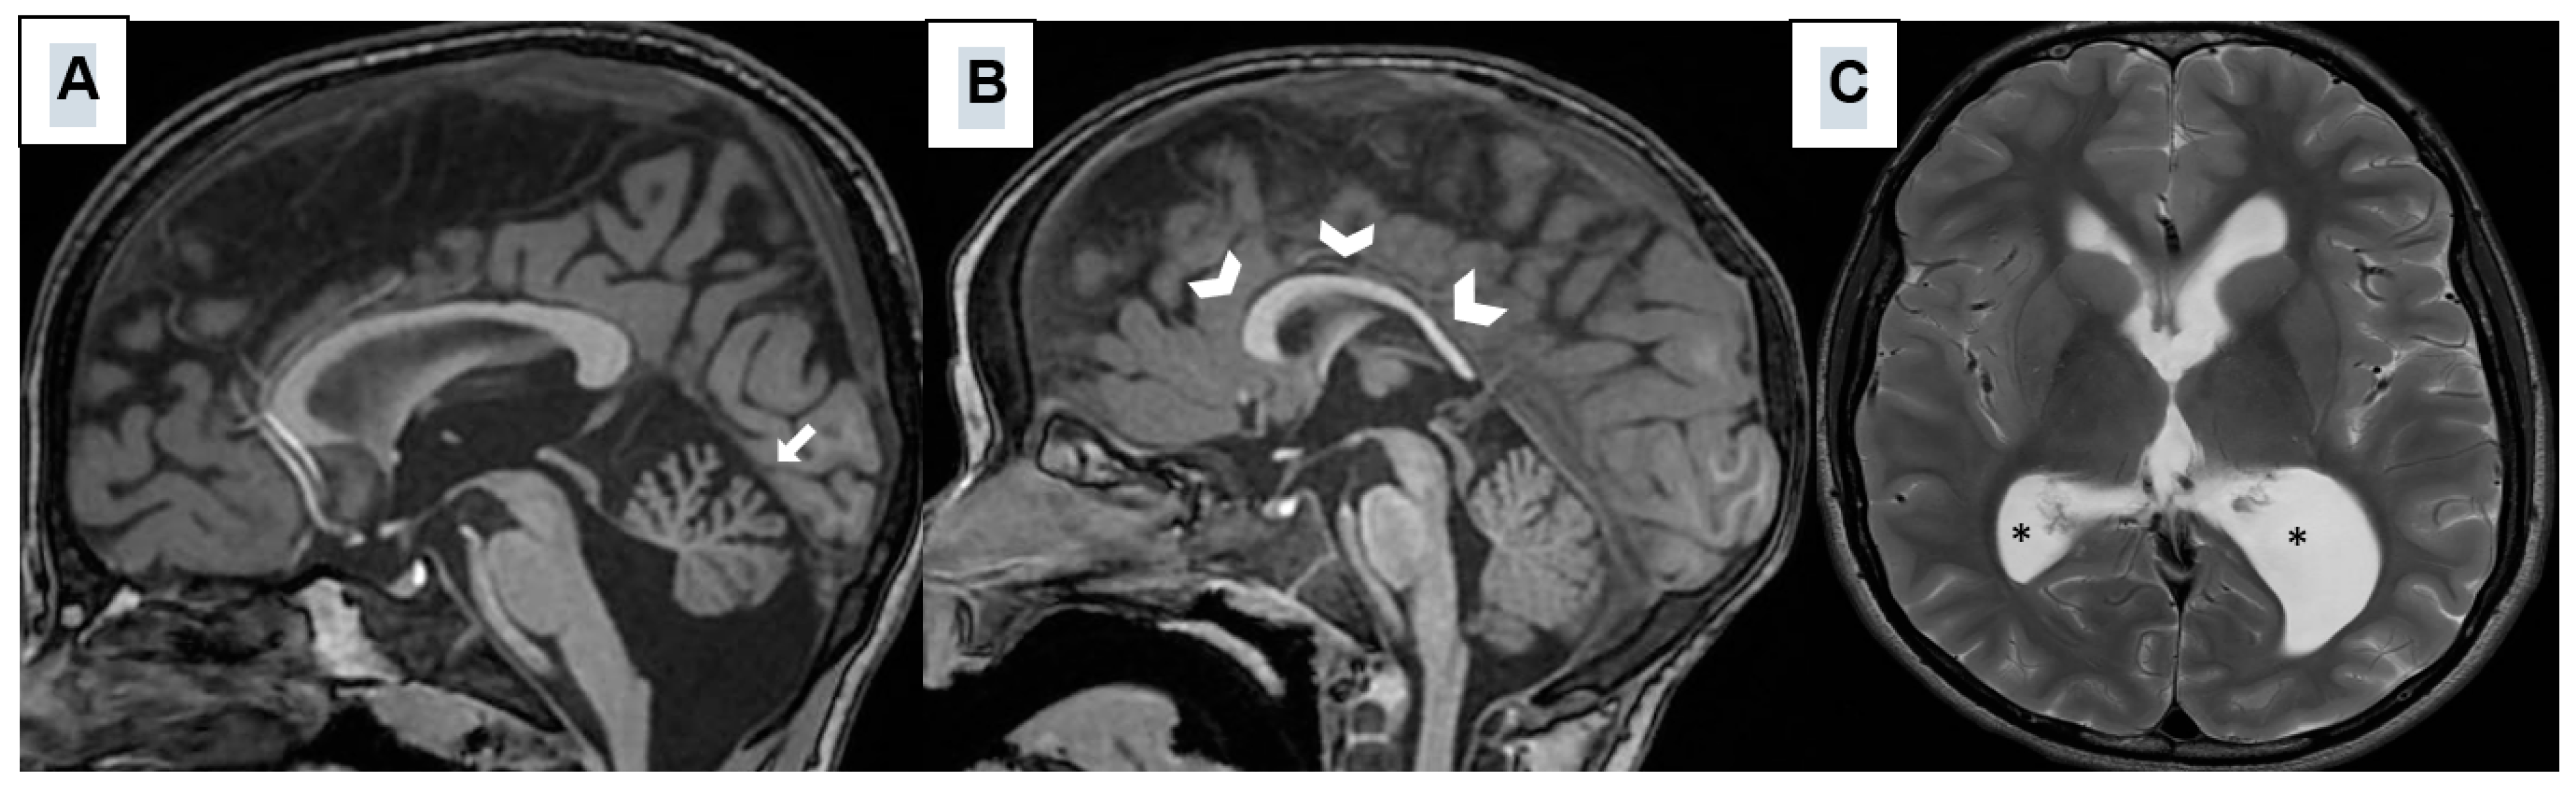

| Neuroimaging Abnormalities | - Cerebellar Hypoplasia (hypoplasia of the cerebellar vermis) - Mild ventriculomegaly - Hypoplastic corpus callosum - Abnormality of cerebral white matter |